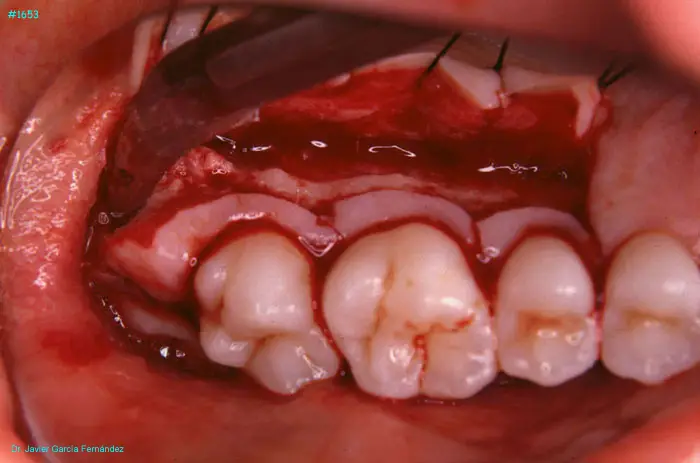

Atlas of Surgical Techniques in Periodontics. Chapter IV. Atlas de Técnicas Quirúrgica en Periodoncia

image 166